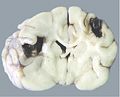

cerebral malacia

Chứng nhũn não là triệu chứng bệnh diễn ra do huyết khối ở não làm tắc động mạch não, dẫn đến máu không thể mang chất dinh dưỡng nuôi não.